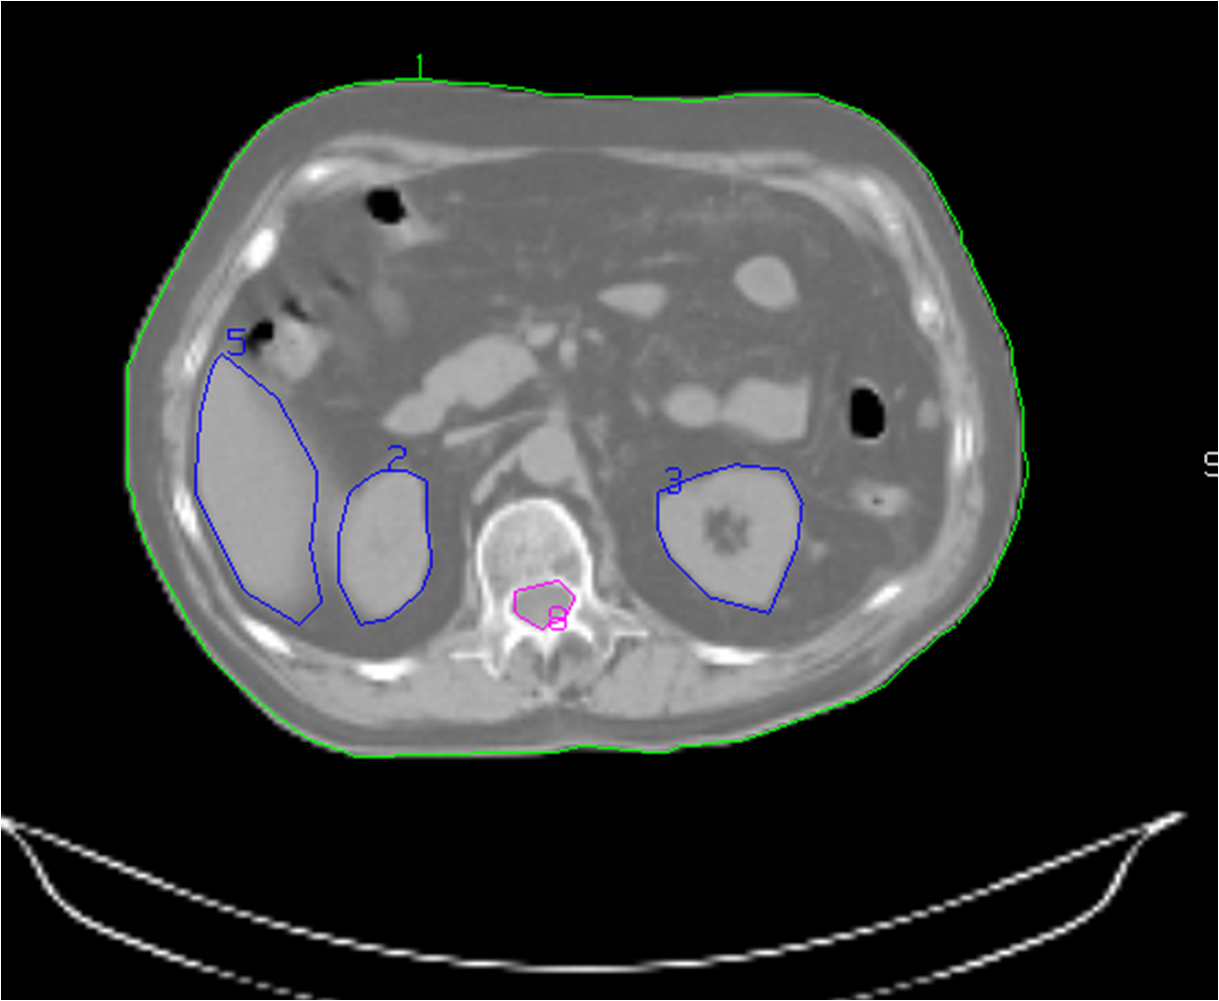

Figure 13, 14, 15: Patient fixation

Figure: 16, 17: Contouring

Figure 18, 19: Treatment planning